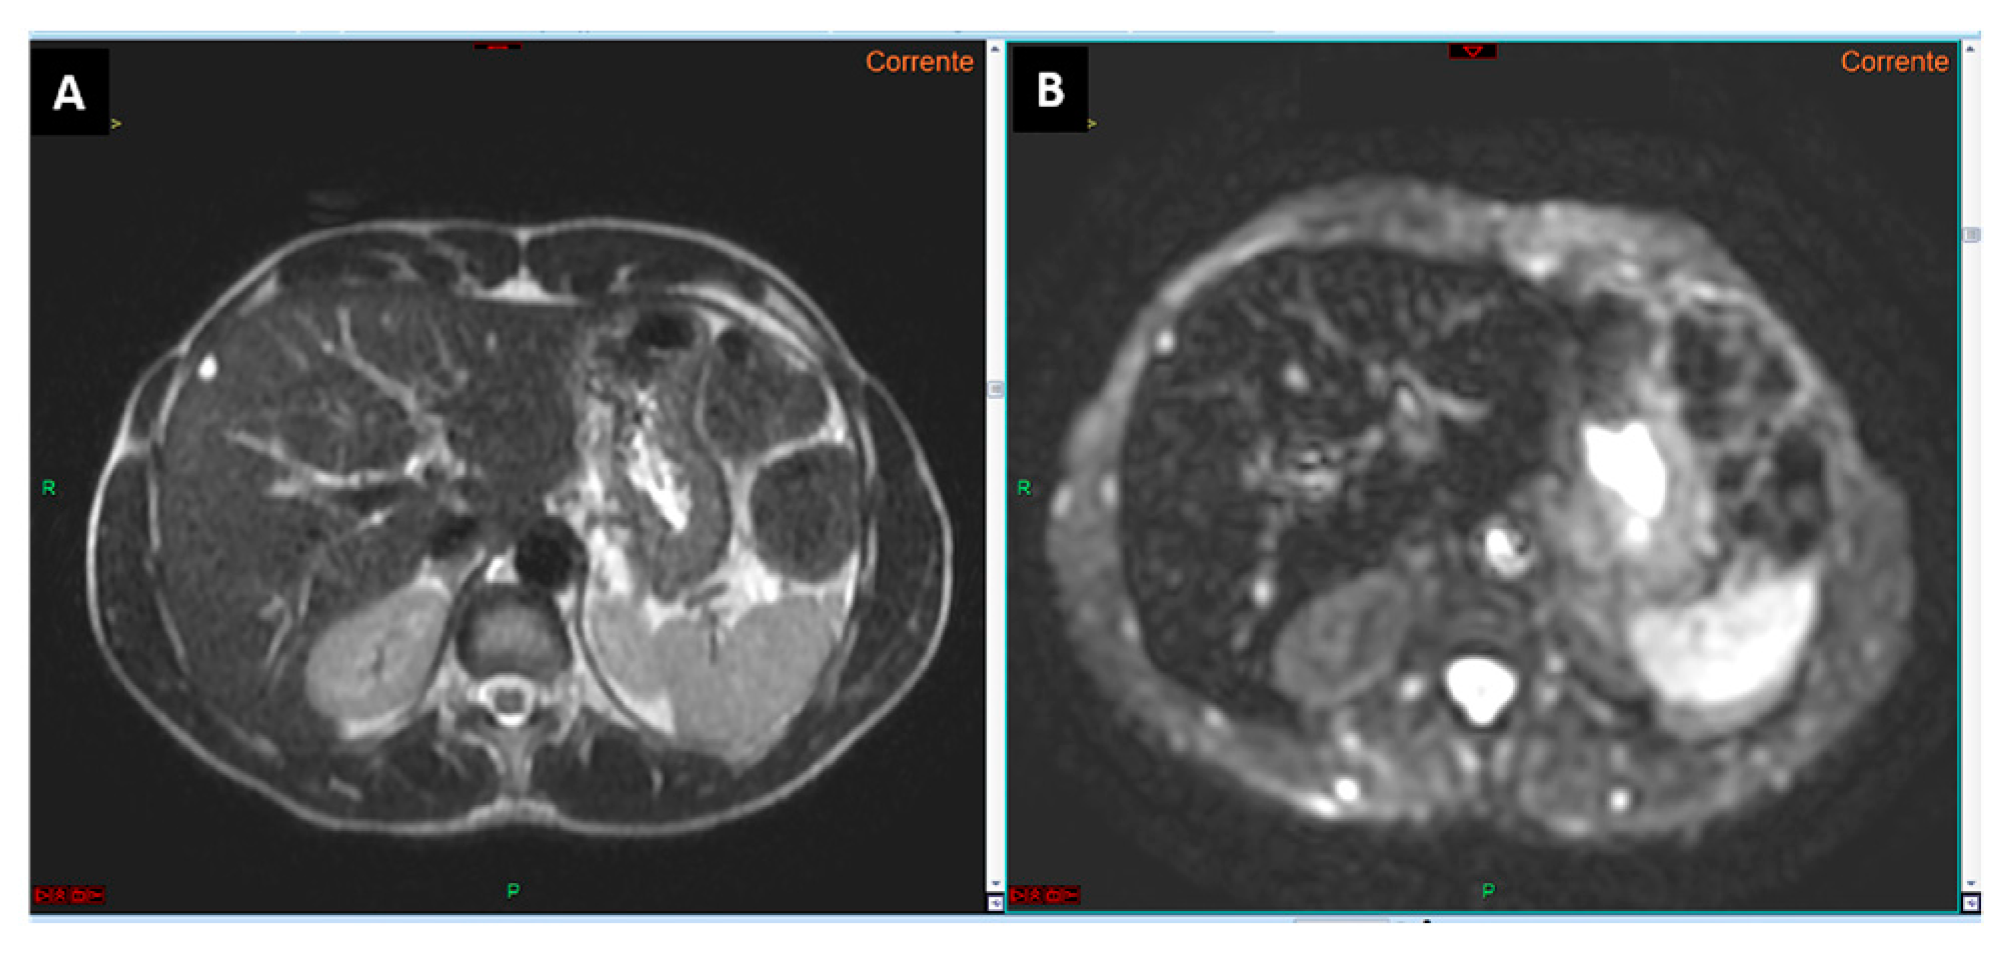

Figure 2.

T2-weighted image (A) and diffusion-weighted image with a b-value 0 (B). It is evident that the diffusion-weighted image (B) corresponds to the T2-weighted imaging (A) in terms of signal intensity, as demonstrated by the signal (hyperintensity) of the small cyst located in the liver segment IV.